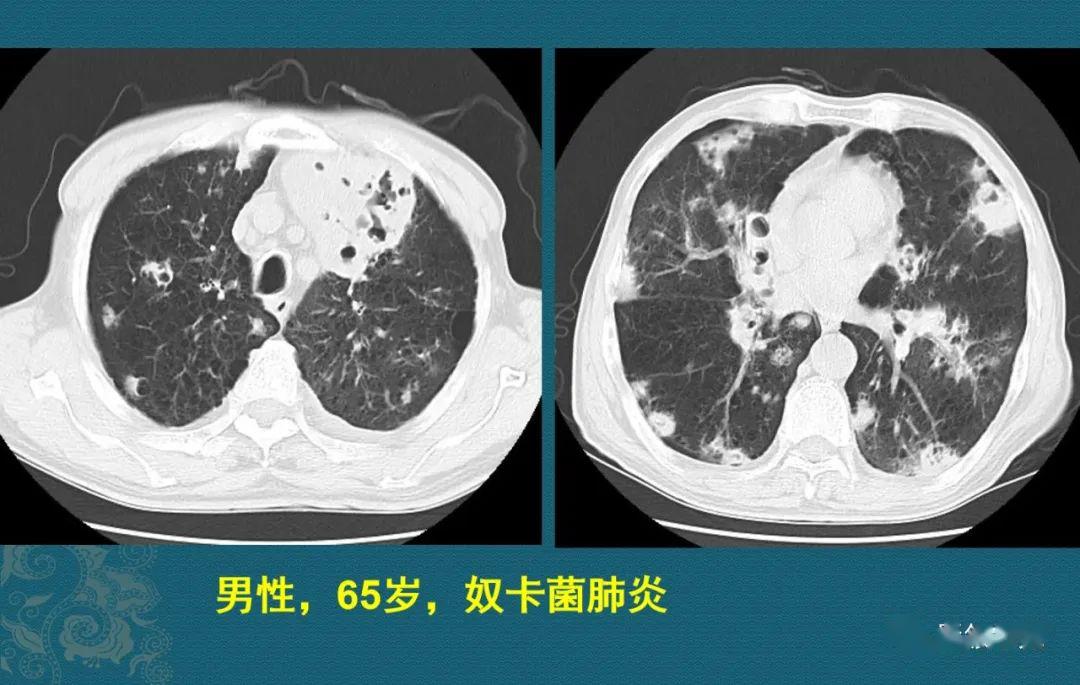

豪哥说肺炎:奴卡菌肺炎趣解